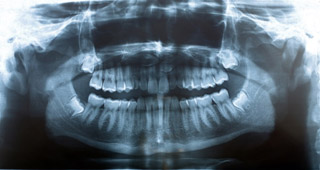

For tooth surgeries (such as wisdom teeth removal and dental implant placement), the essential diagnostic tool is the panoramic X-ray (Panorex). Regular dental X-rays (periapical or bitewing) are inadequate for wisdom teeth because they do not provide the surgeon with a complete picture. Standard dental X-rays have a limited field of view and, therefore, rarely show the wisdom teeth in their entirety. A panoramic X-ray, on the other hand, provides a complete view of the jaw and teeth. The panorex shows the teeth and roots and their stages of development. It also shows their relationship to adjacent teeth, sinuses, and nerve canals. The panorex enables surgeons to accurately diagnose and plan surgeres of the teeth and jaw.